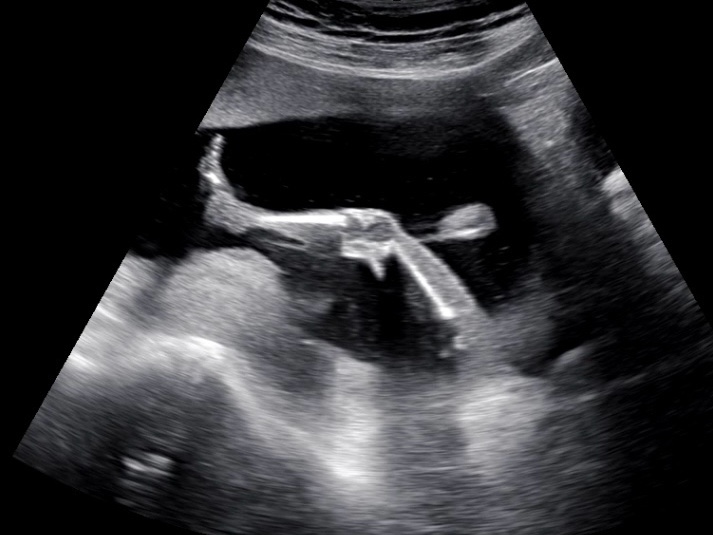

임신일기 / 18주, 19주, 20주 (태동, 경부길이, 아뜰리에슈, 에버랜드, 베이비하우스 영통점, 태교여행, 베이비빌리, 열달후에 태아성장보고서)

드디어 나에게도 임신 황금기가 찾아온 것 같다? 당연히 임신 전에 비하면 멀쩡하지만은 않은 몸이지만 ...